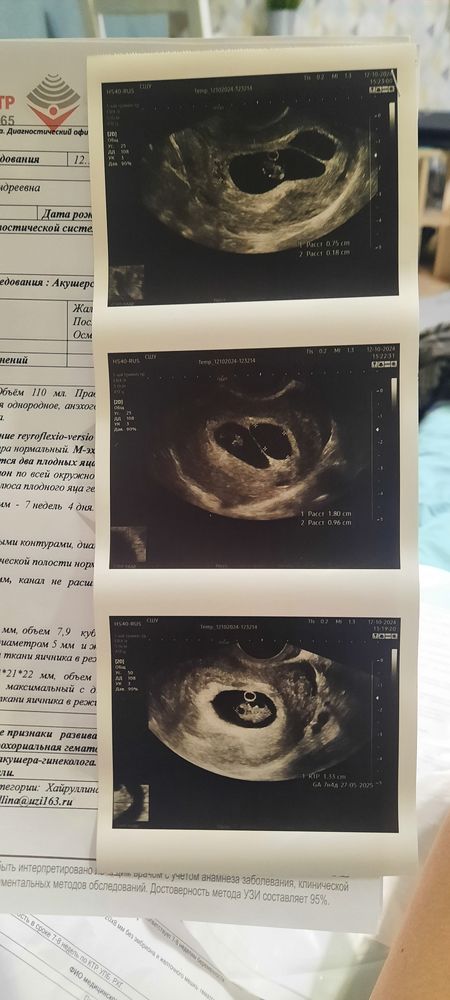

Изображение

13.10.2024

Валентина, вот такой ответ я получила от стороннего репродуктолога. О таком варианте мне до этого ни один врач не сказал и я о таком даже не слышала. Но сейчас понимаю, что он очень вероятен. В первую очередь потому что это якобы "второе плодное яйцо" растёт равномерно вместе с первым, не смотря на отсутствие в нем чего либо.

Лисенок, в следующий раз пойду через 2 недели наверное, или хотя-бы 10 дней постараюсь продержаться. А то я уже 4 узи сделала за 3 недели и везде одна картина-четкое,ровное яйцо, которого быть не должно.

Валентина, если три недели уже чернота, значит, и правда пя, кровь давно бы уже свернулась и стала бы мутной на узи. Будет забавно, если там все же кто-то появится)))